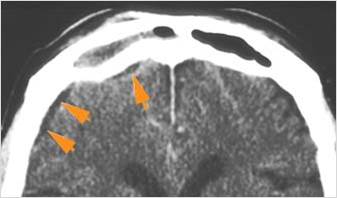

There is a subperiosteal fluid collection or abscess along the boney walls of the anterior or middle cranial fossa.

There is an epidural fluid collection or abscess along the boney walls of the anterior or middle cranial fossa.

There is a subdural fluid collection or abscess along the boney walls of the anterior or middle cranial fossa.

There is a subdural fluid collection or abscess along the falx cerebri or within the tentorium.